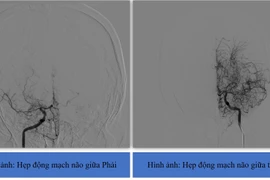

Thay vì phẫu thuật bóc tách nội mạc động mạch cảnh thì nay với sự phát triển của khoa học kĩ thuật phương pháp đặt stent động mạch cảnh sẽ giúp giải quyết tình trạng hẹp gây tắc mạch máu, giảm nguy cơ đột qụy, nhồi máu não.